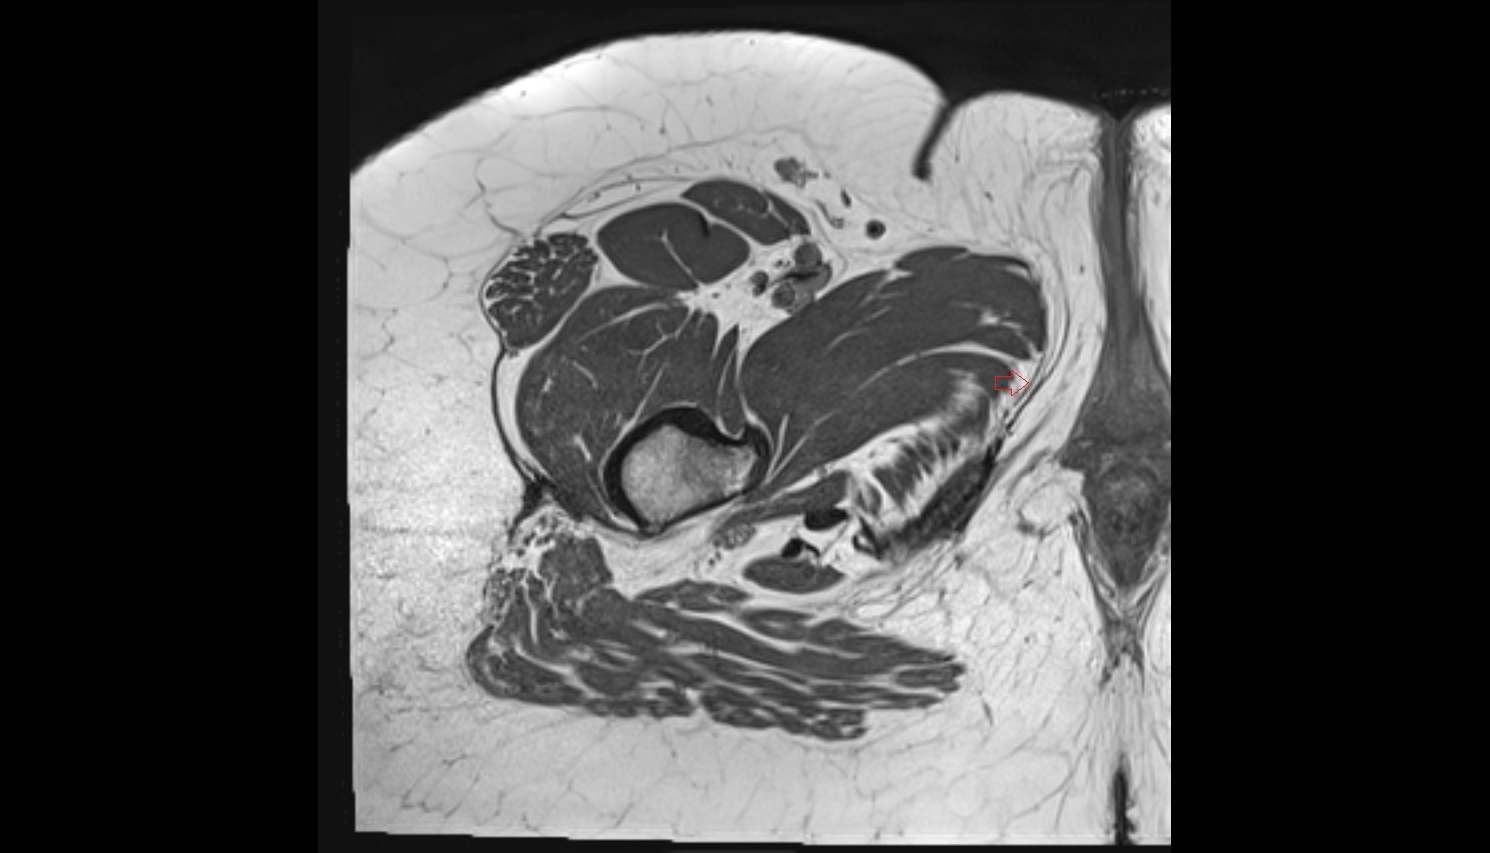

- Uterus

- Body of uterus

- Fundus of uterus

- Cervix of uterus

- Isthmus of uterus

- Vagina

- Fornix of the vagina

- Endometrium of uterus

- Myometrium of uterus

- Perimetrium of uterus

- Junctional zone of uterus

- Ovaries

- Right ovary

- Left ovary

- Fallopian tube